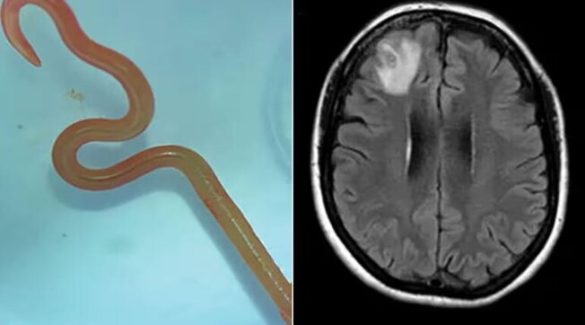

Soffriva di amnesie e depressione, le trovano un verme di 8 cm nel cervello

Soffriva di depressione e vuoti di memoria, una donna di 64 anni, australiana, si รจ … Leggi tutto Soffriva di amnesie e depressione, le trovano un verme di 8 cm nel cervello